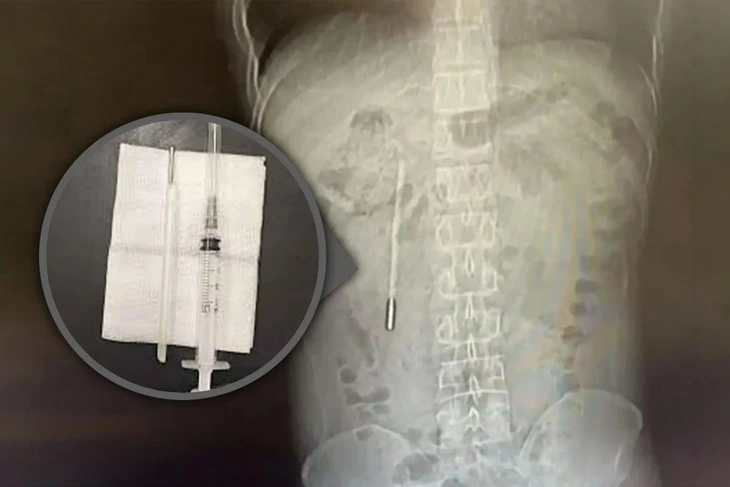

Người thân của cháu N.N.Y (11 tuổi) khi vẩy nhiệt kế do sơ ý chiếc nhiệt kế chọc mạnh vào tay trái của cháu. Chiếc nhiệt kế bị vỡ và tạo ra vết thương ở ngón trỏ tay trái. Do sợ bị nhiễm độc thủy ngân, gia đình đã đưa cháu tới bệnh viện và nhập viện Bệnh viện Bạch Mai ngày 11/02/2021